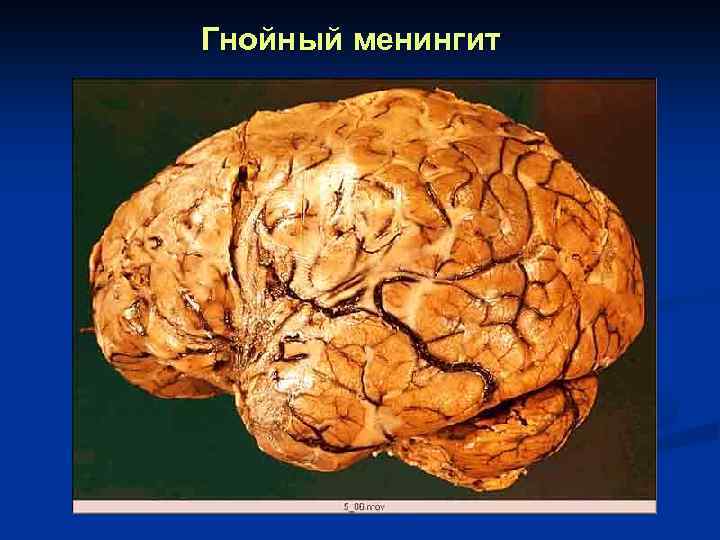

Гнойный менингит